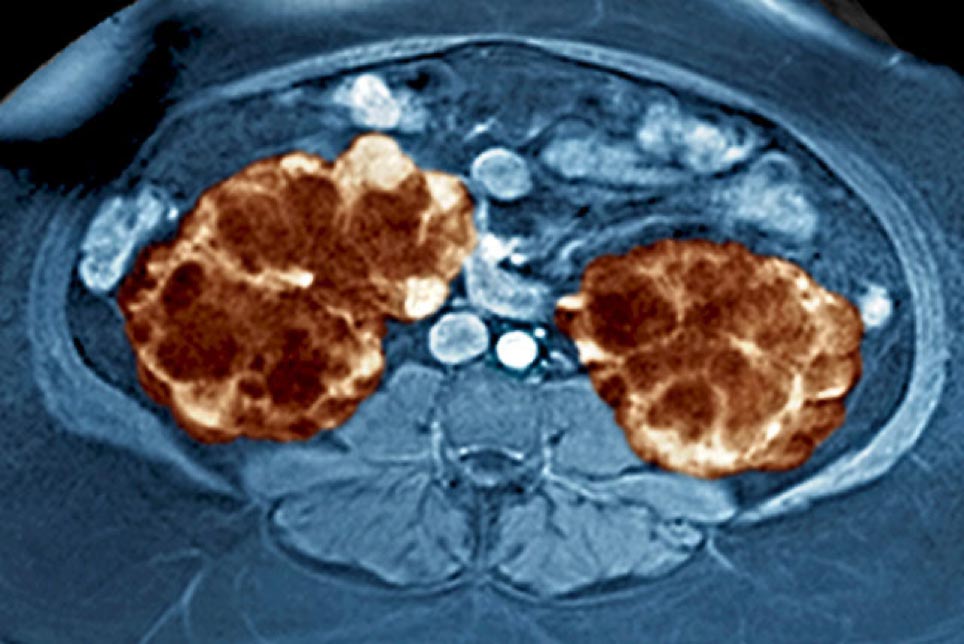

Autosomal dominant polycystic kidney disease

Gabow 1990 talks about autosomal dominant polycystic kidney disease and how this disease is genetic. They go on to say "Autosomal dominant polycystic kidney disease (ADPKD) is the most common genetic disease, affecting a half million Americans. The clinical phenotype can result from at least two different gene defects. One gene that can cause ADPKD has been located on the short arm of chromosome 16." The same article also goes on to say that millions of Americans are affected by this disease and it is very common.

Additional possible cause of nephropathy is due to the formation of cysts or pockets containing fluid within the kidneys. These cysts become enlarged with the progression of aging causing renal failure. Cysts may also form in other organs including the liver, brain, and ovaries. Polycystic kidney disease is a genetic disease caused by mutations in the PKD1, PKD2, and PKHD1 genes. This disease affects about half a million people in the US. Polycystic kidneys are susceptible to infections and cancer.